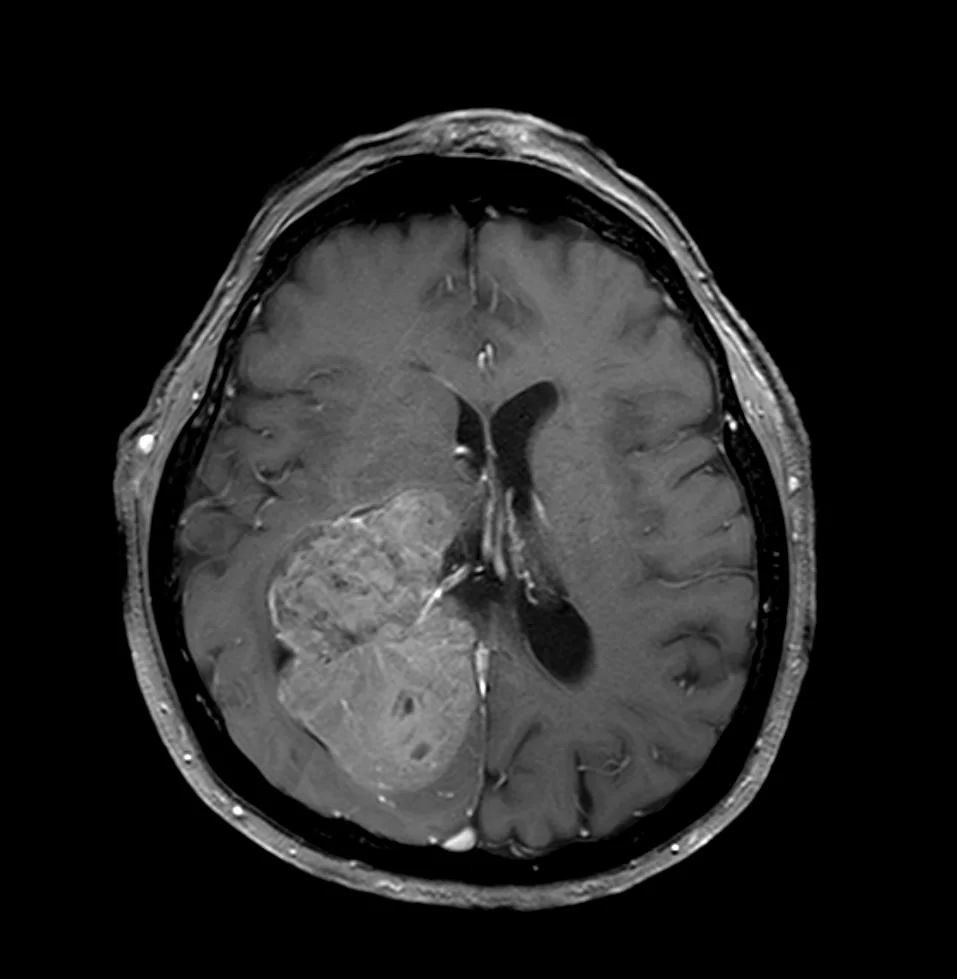

Ευμεγέθες Ενδοκοιλιακό Μηνιγγίωμα Δεξιά

Ασθενής γυναίκα, 70 ετών παρουσίασε επιληπτικές κρίσεις και αριστερή ημιανοψία. Η μαγνητική τομογραφία ανέδειξε ευμεγέθη χωροκατακτητική εξεργασία εντός της δεξιάς